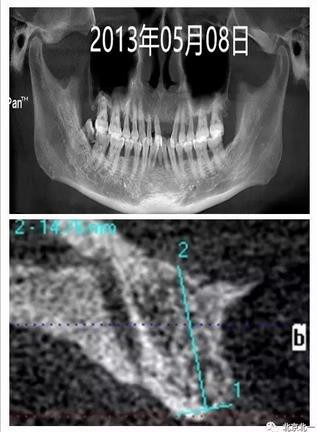

圖一:手術(shù)前CBCT

圖二:微創(chuàng)拔牙即刻種植當(dāng)天,采用ACTIVE 4.3*11.5,3.5*11.5(11 21位點)